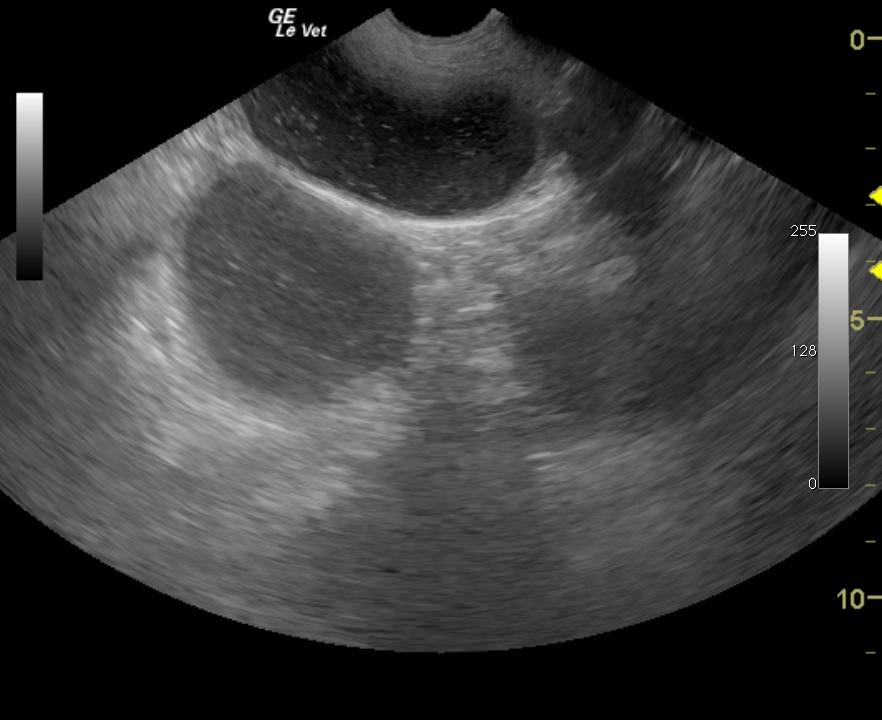

Image 1: Obstruction, severe diffuse intestinal ileus. Image 2: Foreign material, abnormal accumulation of ingesta and focal intestinal stasis

Image and Video 1: Generalized small intestinal fluid dilation. Image and Video 2: Small intestinal focal irregular hyperechoic echo with distal acoustic shadowing.